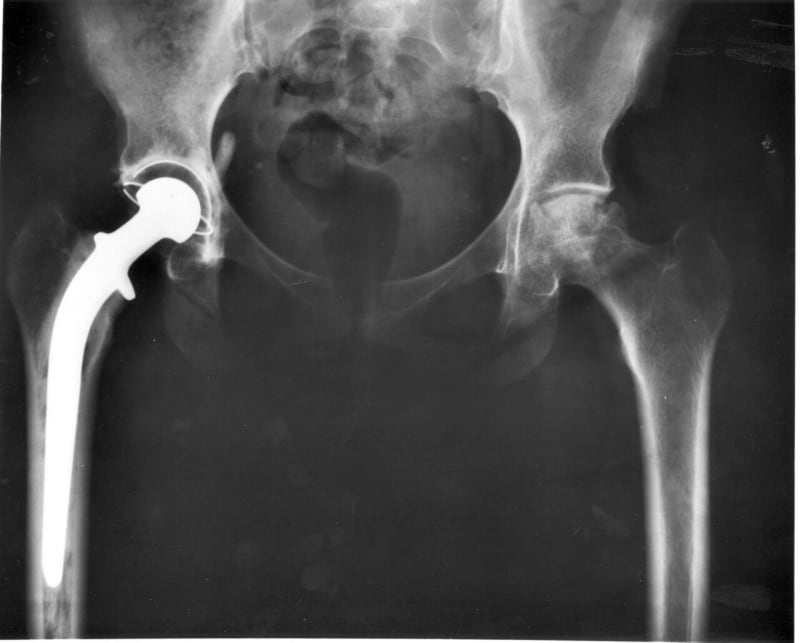

A groundbreaking study published in The Lancet reveals that modern hip replacements are lasting nearly twice as long as their predecessors. Researchers analyzed data from 1.9 million hip replacements across eight national registries and found that 92% of today's implants remain functional for at least 25 years.

The secret lies in better materials. Over the past two decades, advances in the materials used for hip replacements have dramatically reduced wear and tear. These modern implants don't just last longer at 25 years; the research suggests 93% could still be working after 20 years, and 91% might make it to 30 years.